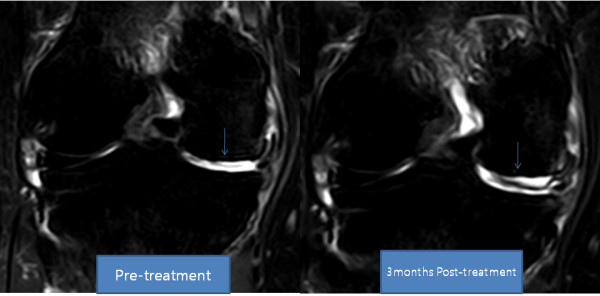

- J. Pak, “Regeneration of human bones in hip osteonecrosis and human cartilage in knee osteoarthritis with autologous adipose-tissue-derived stem cells: a case series,” Journal of Medical Case Reports, vol. 5, p. 296, 2011. View at Publisher · View at Google Scholar · View at Scopus